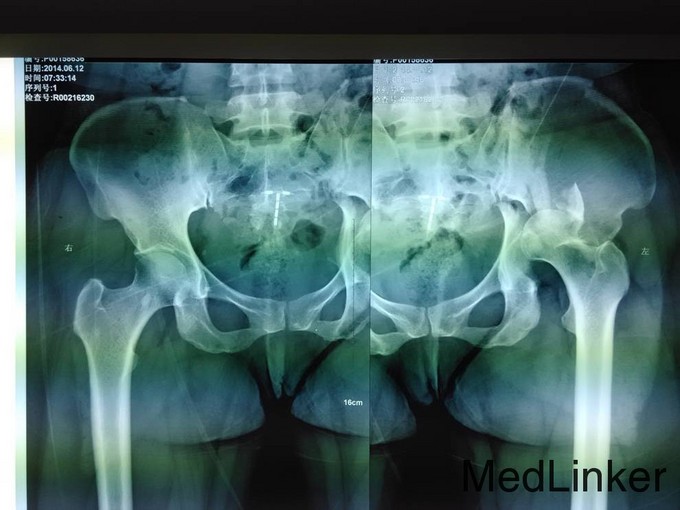

主诉:车祸外伤后左髋部疼痛伴活动受限4天 患者于2014年6月12日早6点左右被皮卡车撞伤,伤后患者出现一过性昏迷,被急诊送往当地医院,行DR及CT检查后,诊断为:左髋臼骨折,于当地医院骨科行骨牵引、抗炎补液等对症治疗后,现为求进一步治疗转入我科,患者病来无头晕头痛,无恶心呕吐,已排气排便.

患者左下肢股骨髁上骨牵引中,左髋部肿胀,臀部可见淤血瘀斑,骨盆分离挤压试验(+),左大腿肿胀,左下肢无明显短缩,纵向叩击痛(+),左下肢小腿外侧及足背麻木感,足背伸肌力正常,双足趾可活动,双侧足背动脉可触及搏动